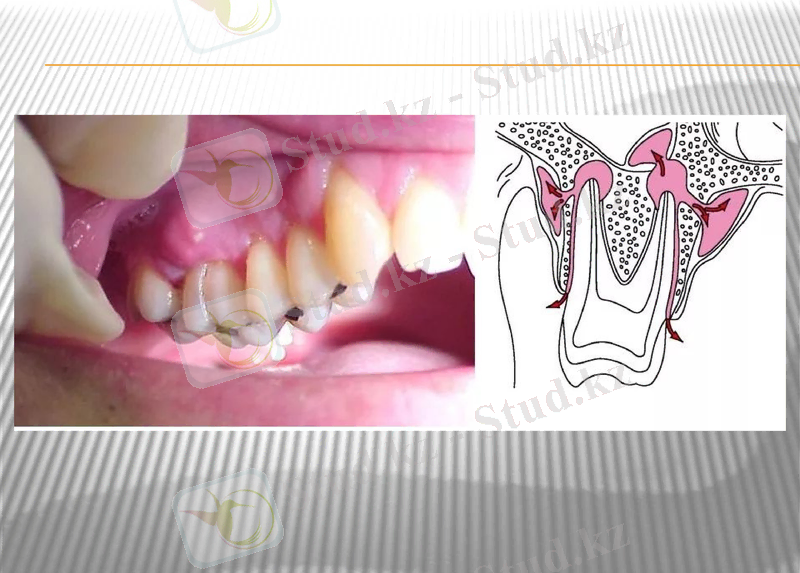

Іріңді периостит /periostitus pirilenta/ сүйек қабығының балқып, тесіліп, абцесс пайда болумен сипатталатын сүйек қабығының іріңді қабынуы.

Ауыр ағында өтсе кариеске, сүйек некрозына, тіпті остеомиелитке айналуы мүмкін.

Клиникалық белгілері: температура көтерілуі, әлсіздік, жергілікті ісік, қатты ауырсыну, ақсау.

Остеомиелит- жақ сүйектері кемігінің қабынуы. Көбінесе өршімелі іріңді перицементиттен туындап, астыңғы жақ сүйегінде үлкен азутістердің тұсында дамиды. Остеомелит жедел және созылмалы ағымды . әдетте іріңдіпреиодонтитпен сырқаттанып, организмі бактериялық стрептокок, жасыл іріңді таяқша, коли-таяқша сияқты антигенмен байқалады. Алдымен альвеоларлық өскіннің кемікті кеңістігі іріңдейді кейін жақ сүйек денесіне жайылады. Ол жерде сүйек табақшалары лакуналы не тегіс сипатта ыдырап жұқарады.

Микроциркуляциялық арнаның тамырларында тромбылар түзіліп саңылауы бітеліп, сүйектің кей жерлері өлескеге айналады, бөлініп сүйектік секвестр қалыптасады. Секвестр іріңмен қошалып секвестрлік қуыста орналасады. Үдеріс ұзаққа созылса пиогенді мембрана пайда болады. Мембрана ішіне лейкоциттер толады. Грануляциялық тінінің сыртқы қабатында талшықты дәнекер тін өсіп қабыққа айналып секвестрлік қуысты сүйектен шектейді. Кейде іріңнің әсерінен секвестрлік қабықпен сүйек жіне оның қабығы дажидеп жыланкөз қалыптасып секвестрлік қуыс ауыз қуысыпен жалғасады, бет терісі арқылы сыртқа шығады. Секвестр сыртқа шығарылған соң жаңа сүйек табақшалары пайда болады.